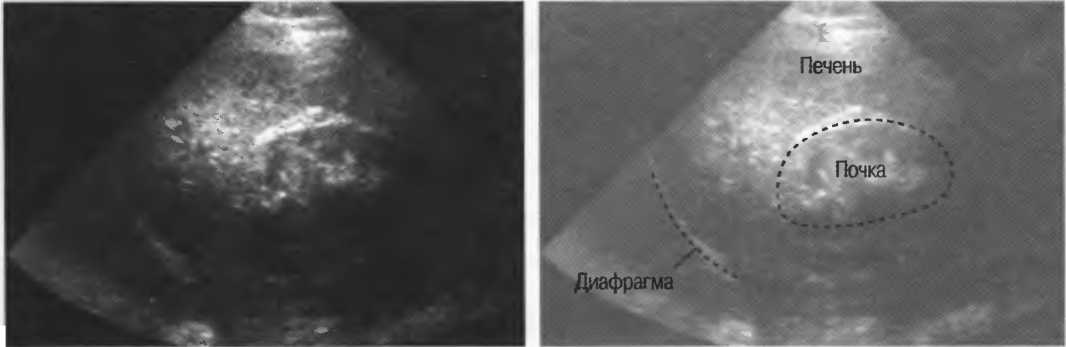

4. У здоровых обследуемых паренхима печени должна быть немного более эхогенна. чем кора рядом расположенной почки (рис. 26).

Рис.26. Продольный срез через печень и правую почку: нормальная паренхима печени более эхогенна, чем паренхима нормальной почки. Это еще один способ проверки качества изображения.